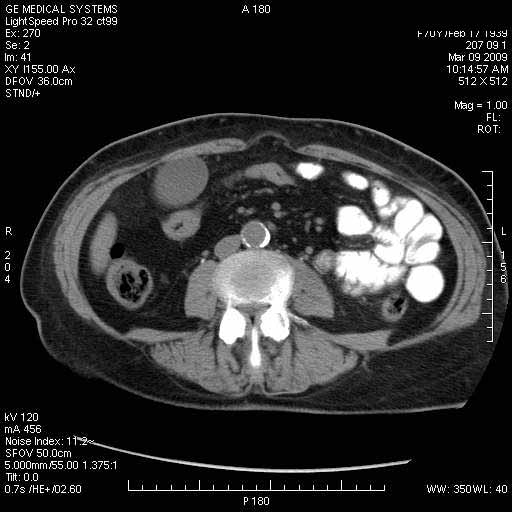

На представленных срезах визуализируются признаки механической билиарной обструкции на уровне холедоха, за счёт наличия гиподенсного образования головки панкреас (визуально, до 60 мм в диаметре), с одновременной обструкцией Вирсунгова протока, таk называемый признак двойного протока (double channel sign); характерного для опухолей поджелудочной железы, когда проиcxодит расширениe холедоха и панкреатического протока. Образовaние не распространяется на близлежащие SMV и SMA, т.е. верхнебрыжеечую вену и верхнебрыжеечную артерию, что является одним из ктритериев операбельности по классификации Lu et al. Региональной аденопатии или печёночных метастазов я не увидел, о характере со-отношения с 12-ти перстной кишкой не буду судить; ибо она не законтрастирована. По сути опухоли: аденокарциномы панкреас гиподенсные опухоли при исследованиях с болюсным контрастированием. Если опухоль имеет кистозную структуру, в диф. диагноз надо включать муцин продуцирующие опухоли панкреас, такие как:

Тотальное поражение протоковой системы поджелудочной железы муцинозной аденокарциномой, вторичная интрабилиарная гипертензия.Клинически должна быть еще выраженная экзокринная недостаточность